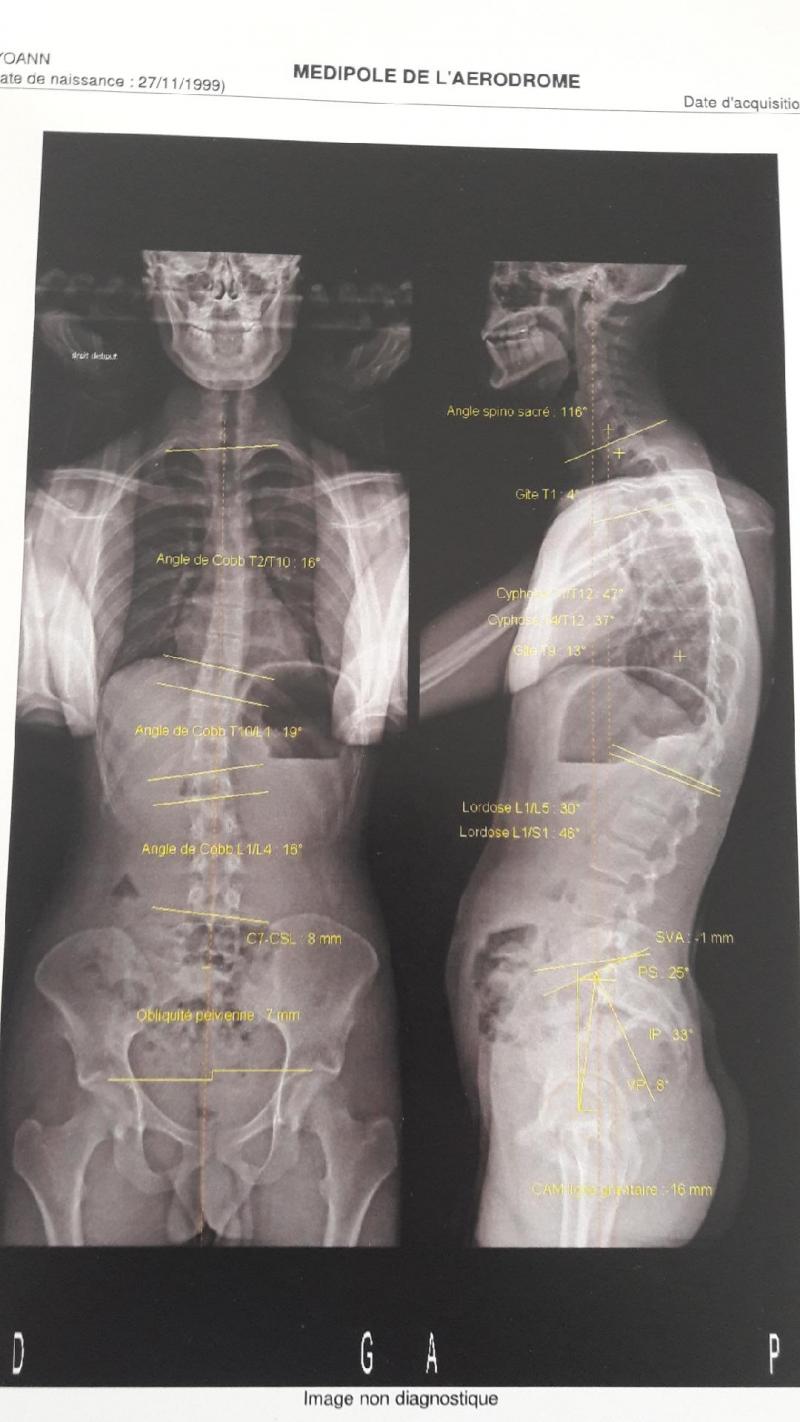

ps: voici le scanner de 2020 de mon dos et mon bassin qui me provoque ces douleurs